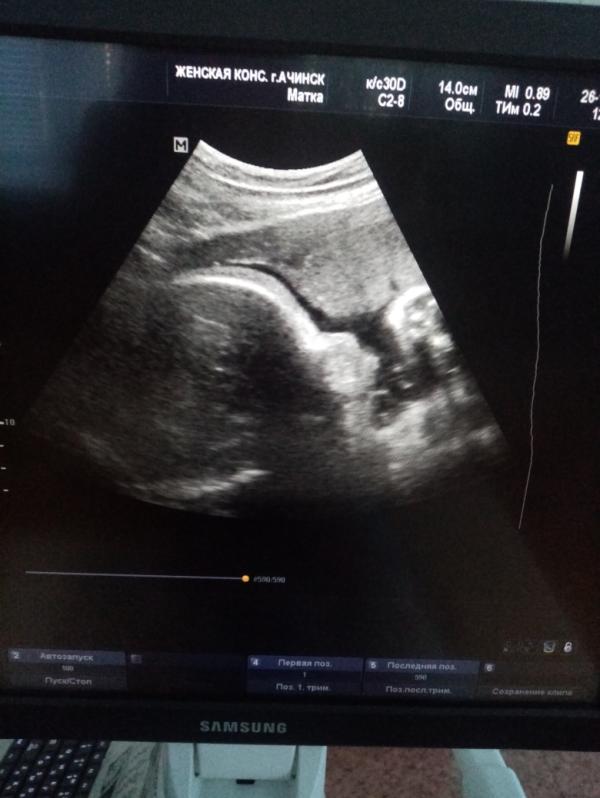

Почему такая большая голова?или это не голова?

Ребёнок уже большой, не влазит на весь экран, если только картинку уменьшить, когда запись делала на диск у Васильевой она так сказала)

Что 29 см ? Голова ? Вам же заключение пишут . Что написано там

@kirill060119 окружность головки 297 мм, размеры плода пропорциональны, соответствуют сроку беременности.

@ksenia6789, ну и всё) что вы переживаете, написано же что соответствует 😌

Голова конечно) если по узи размеры норм то все в порядке